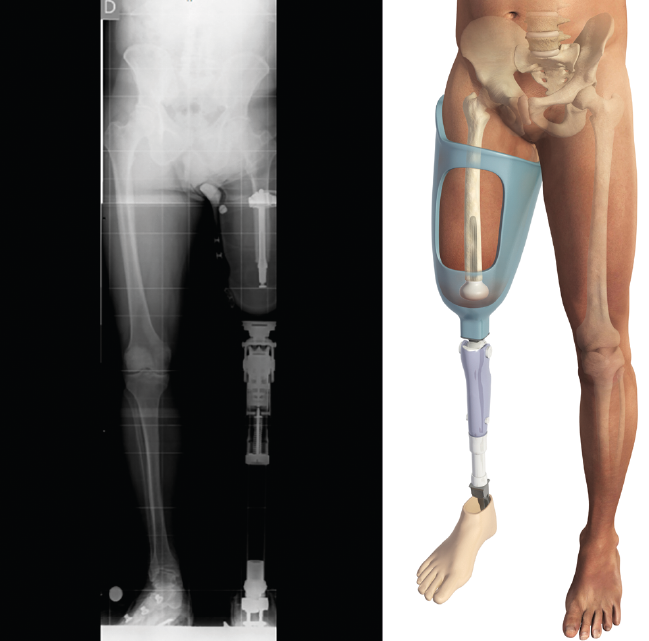

Figura 5. Telemetría del implante Keep Walking® en el paciente protetizado donde se puede apreciar la alineación del encaje.

Las longitudes del vástago oscilan entre 120 y 180 mm, el diámetro de 11 a 17 mm y los diámetros de espaciador oscilan entre 54 y 62 mm. Finalmente, se monta el implante definitivo y se inserta impactado a press-fit en el fémur. Los tejidos blandos son suturados realizando una correcta mioplastia alrededor del espaciador (Figuras 4 y 5).

Figura 8. Encaje definitivo con carga distal.

El encaje definitivo se realiza aproximadamente a los 3 meses del encaje provisional, una vez que el volumen del muñón se ha estabilizado. Este es el encaje que aprovechará completamente las ventajas del apoyo distal para su caso concreto. Aunque los encajes se realizan con técnicas estándar, es necesario que el técnico ortopédico adapte el encaje y los desarrolle de manera que aproveche las ventajas del implante Keep Walking®(Figura 8).